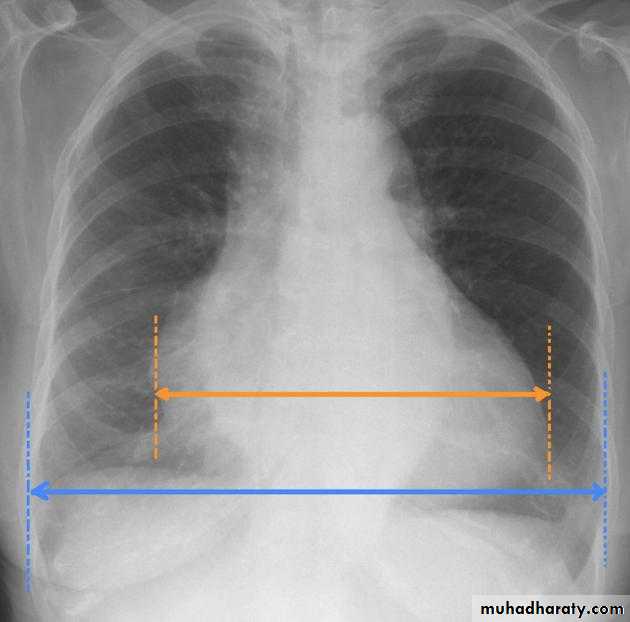

• chest radiography (cardiomegaly is suggestive of hypertensive heart disease);

Measurement of cardiothoracic ratio ( CTR)